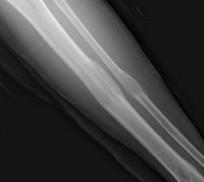

Аноним Пнд 24 Мар 2014 19:54:22  #22 №64952639

смотрю на всех кто выше как на говно

проезжая вальяжно мимо

а их тян\жены уже жалеют что с ними